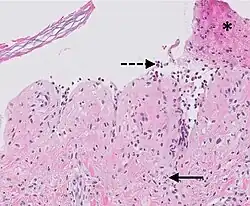

| Prevesicular stage of bullous pemphigoid | Image at right shows influx of inflammatory cells including eosinophils and neutrophils in the dermis (solid arrow) and blister cavity (dashed arrows), and deposition of fibrin (asterisks).[15] However, the diagnosis of bullous pemphigoid consist of at least 2 positive results out of 3 criteria:[19]

|